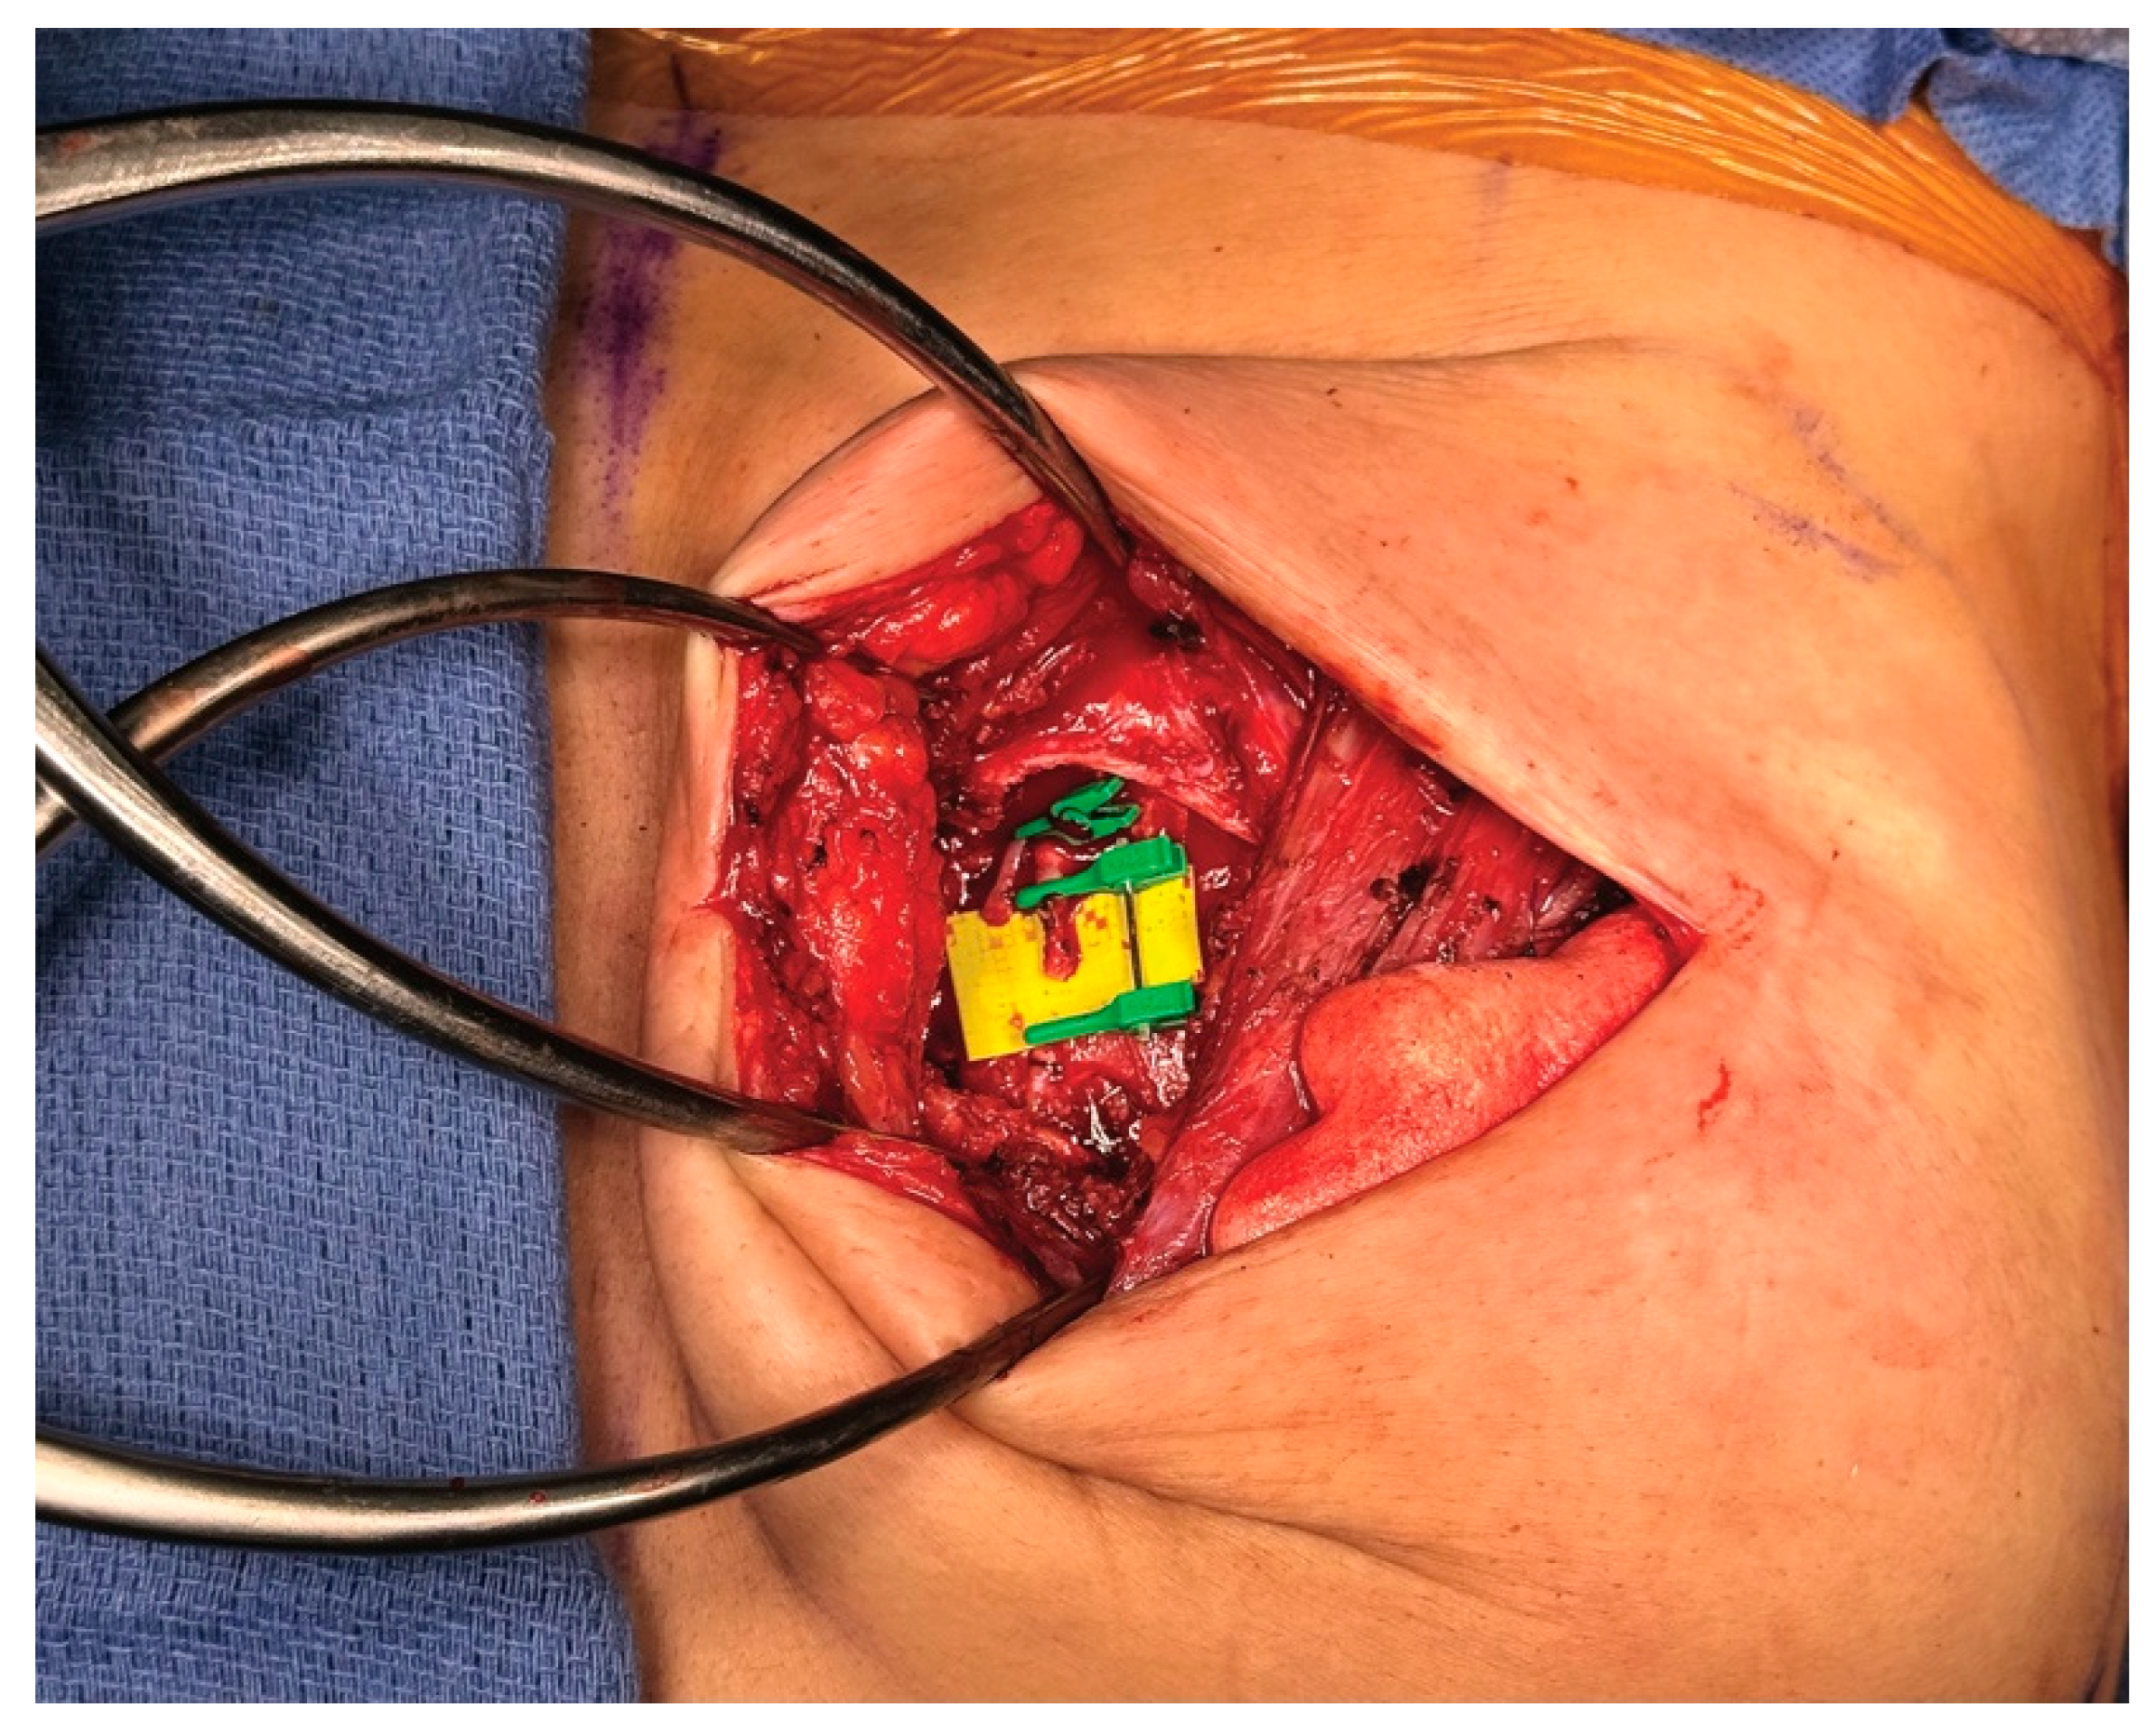

4.3. Case 2—HyPAD®

4.4. Operative Technique